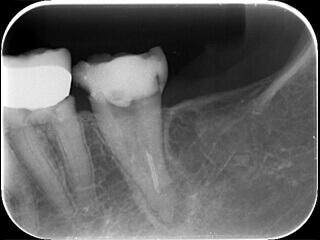

症例1 神経を取っても痛みが取れない

2

膿を出す目的で根管が開放(ガイドラインでは推奨されていません)がされていました。

3

ホルマリンと思われる強い刺激臭がします。

4

綺麗に治療されているように見えます。

5

感染(虫歯など)のみに色がつく染色液です。神経は取れていますが、感染が残ってしまい痛みが残っていました。

6

虫歯を除去し再度バイ菌が入らないよう壁を作ると痛みは無くなりました。(隔壁と言います)